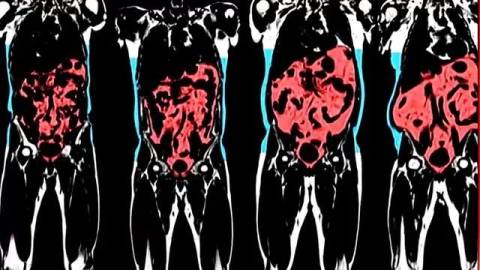

这一方法要比BMI更有助于人们了解自己体内是否堆积过多的内脏脂肪(visceral fat),内脏脂肪通常聚集在心脏、肝脏和胰脏周围,会增加糖尿病、心脏病和高血压的风险。